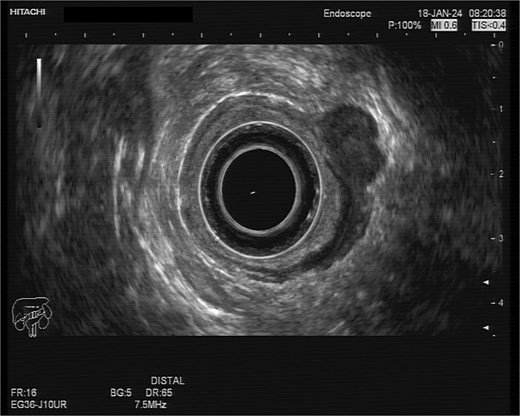

A 75-year-old woman with a past surgical history of serous papillary ovarian carcinoma underwent complete debulking surgery and adjuvant chemotherapy treatment 2 years prior to her current presentation. During follow-up, increased FDG uptake along with a 1.2-cm mass was seen on a PET-CT on the serosal surface of the recto-sigmoid junction (Fig. 1). An attempt was made to evaluate the lesion using trans-rectal sonography. Radial sonographic view showed a 12 mm, hypoechoic, well-defined lesion located at the serosal surface of the recto-sigmoid junction (Fig. 2). After reverting to a linear view, the lesion was sampled with fine-needle biopsy (Fig. 3) and whitish thick cores were retrieved (Fig. 4). The procedure was uneventful and no adverse events were noted. Pathology revealed fragments of high grade serous carcinoma of tubo-ovarian origin. Relying on the histological information gained from the biopsy, it was known that the lesion although not obvious to the eye during surgery, had to be found and resected. The surgical procedure was challenging with multiple adhesions, which made it difficult to locate the lesion. Based on the valuable preoperative knowledge, the patient was able to have a complete debulking of the tumor mass.

Linear view of the malignant lesion seen as a hypoechoeic mass with biopsy needle inside.